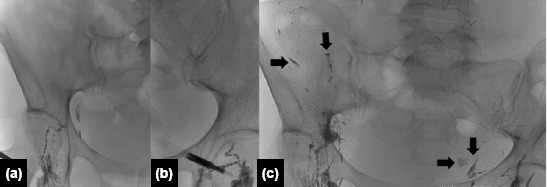

Methods: Between April 2018 and July 2022, eight patients who underwent IL for CL following thyroid and thoraco-abdominal surgeries were included in this retrospective study. Among these eight patients, six underwent bilateral total thyroidectomy, one underwent lobectomy of the lung, and one underwent total abdominal hysterectomy with bilateral salpingo-oophorectomy. Prior to the procedure, thoracic duct ligation was attempted in one patient. Lymphangiographic findings, technical and clinical success rates, and complications were analyzed. Technical success was defined as the successful ultrasound-guided puncture of an inguinal lymph node and the opacification of the lymphatic system in the pelvis and abdomen by fluoroscopy. Clinical success was defined as a progressively decreasing drain output, culminating in the cessation of output within one week after the procedure.

Results: Technical and clinical success was achieved in all patients. On lymphangiography, ethiodized oil leakage near the surgical bed was identified in seven of the eight patients. The median time from the procedure to drain removal was three days (range: 1-6 days) for patients who underwent surgical drainage. No recurrence of CL, chylothorax, or chylous ascites was observed during the follow-up period (range: 21-73 months; median: 38 months).